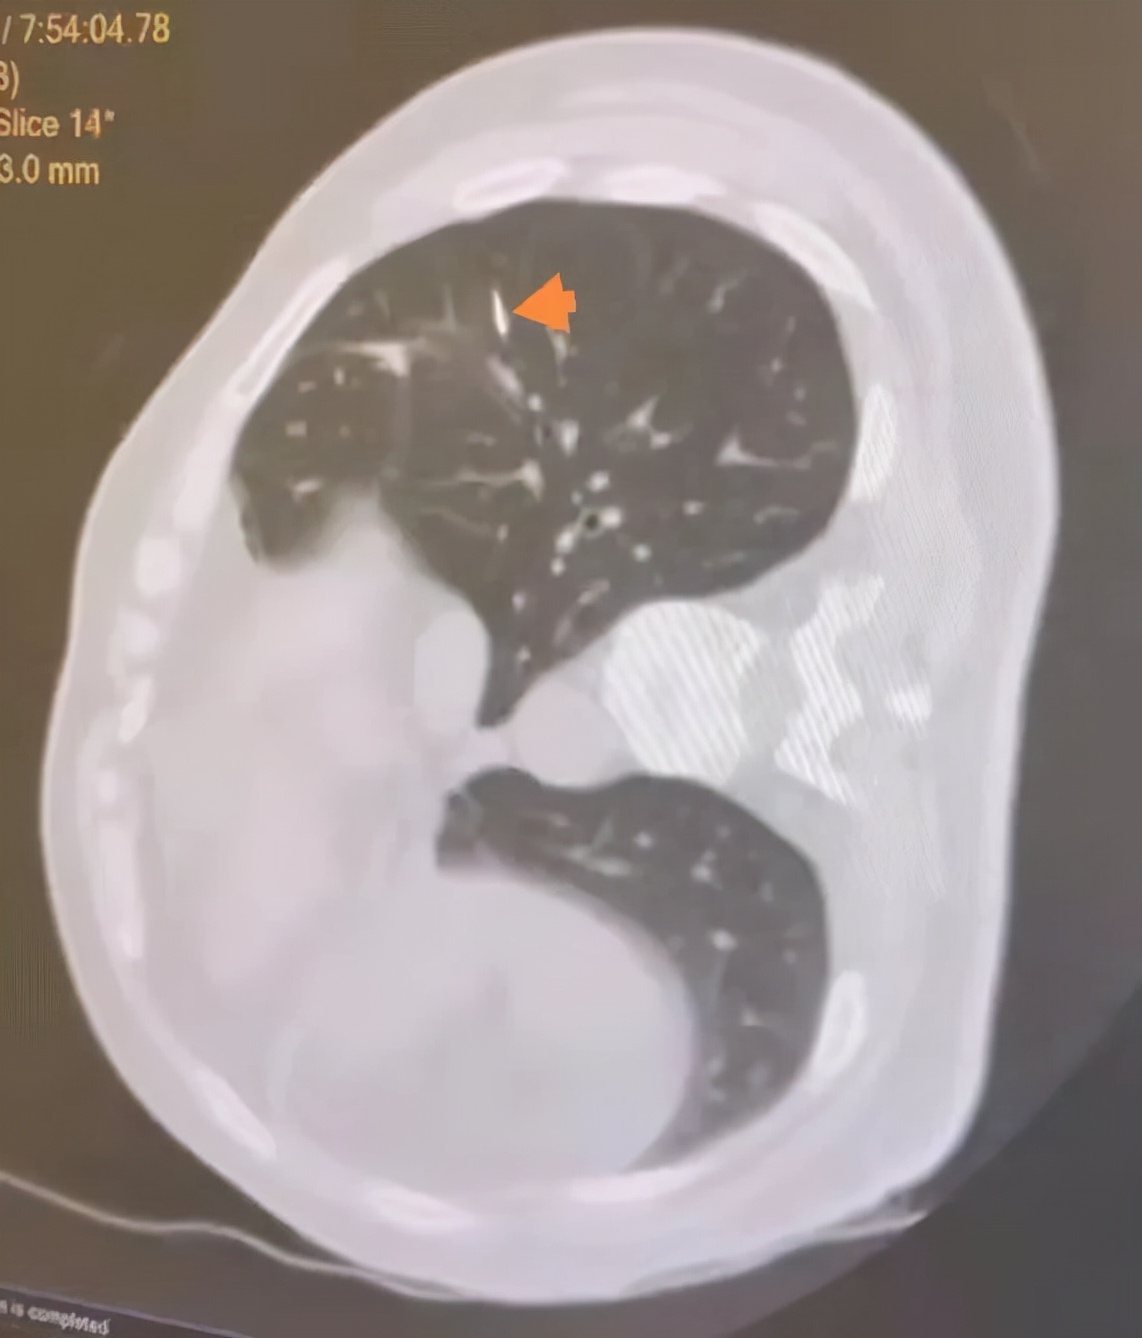

手术之前首先进行CT引导下经皮肺穿刺定位,在CT引导下将定位针放置在肺结节旁边。但是因为结节较小,而且紧贴靠肺动脉分支,穿刺过程中极容易引起肺内血肿,肺内出血更会加剧寻找结节的难度。在放射科的帮助下,我们通过术前CT定位,将穿刺针放置在结节下方约2cm左右的位置,术中根据定位针的位置在其下方行经胸腔镜肺楔形切除手术,不仅能够保证完整切除结节,且切缘距肿瘤能够保证有足够的距离。

箭头所指即为穿刺针定位最终位置